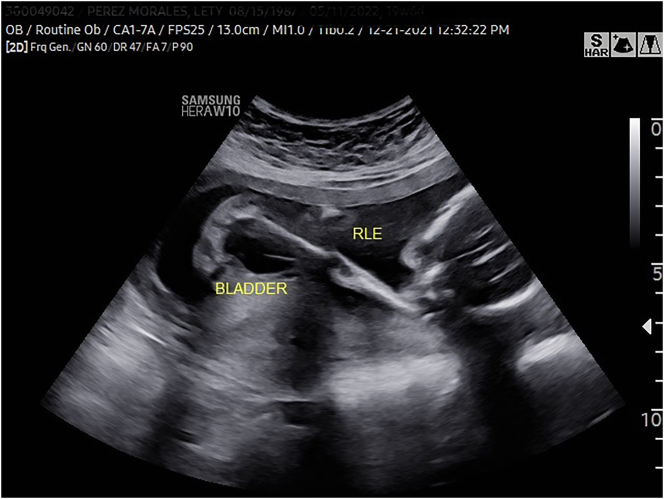

Case presentation: We present two cases of LCCS2, a rare autosomal recessive disorder in the arthrogryposis multiplex spectrum of syndromes whose sine qua non feature is the presence of nonobstructive, neurogenic megacystis. The prenatal diagnosis of this syndrome has not been previously reported. This syndrome has been previously studied in detail in an Israeli-Bedouin kindred but it has not been reported in the Americas.

Abstract Image